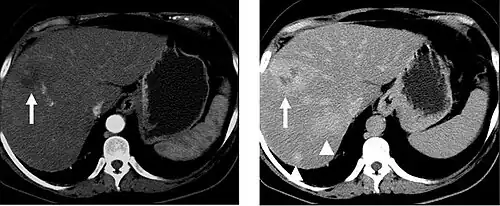

The late arterial phase is timed to correspond to the peak concentration of contrast material in highly vascular tumors and is performed approximately 20–35 seconds after the injection of intravenous contrast. Early arterial phase imaging is predominantly utilized for angiography and will be discussed separately. Late arterial phase imaging is almost always performed in conjunction with other phases (e.g. portal venous phase) to allow more complete characterization of any identified abnormalities (figure 4). The primary indication for a late arterial phase is for the evaluation of hypervascular tumors of the liver such as hepatocellular carcinoma or hypervascular metastases (figure 4). Typical hypervascular tumors for which this would be used include: hepatocellular carcinoma; renal cell carcinoma; melanoma; carcinoid/neuroendocrine tumors; some sarcomas; choriocarcinoma; and thyroid carcinoma. Although a "hypervascular", biphasic evaluation would generally be used for these patients, note that a single phase is often adequate for follow up imaging.

When evaluating hepatic masses, it can be advantageous to have both late arterial and portal venous phase images (biphasic imaging, figure 4) since some tumors enhance briskly during the arterial phase (hepatocellular carcinoma, hepatic adenoma, follicular nodular hyperplasia (FNH), and hypervascular metastasis), but may be occult or difficult to characterize on portal venous phase imaging alone (figure 6). However, it should be stressed that the addition of late arterial phase images is only indicated if one of these tumors is suspected, or if there is a need for further characterization of a hepatic mass, since the large majority of patients will not benefit from the addition of this phase. In addition, if there is a need to definitively characterize a hepatic mass, MRI is generally more sensitive and specific, with no associated radiation dose.